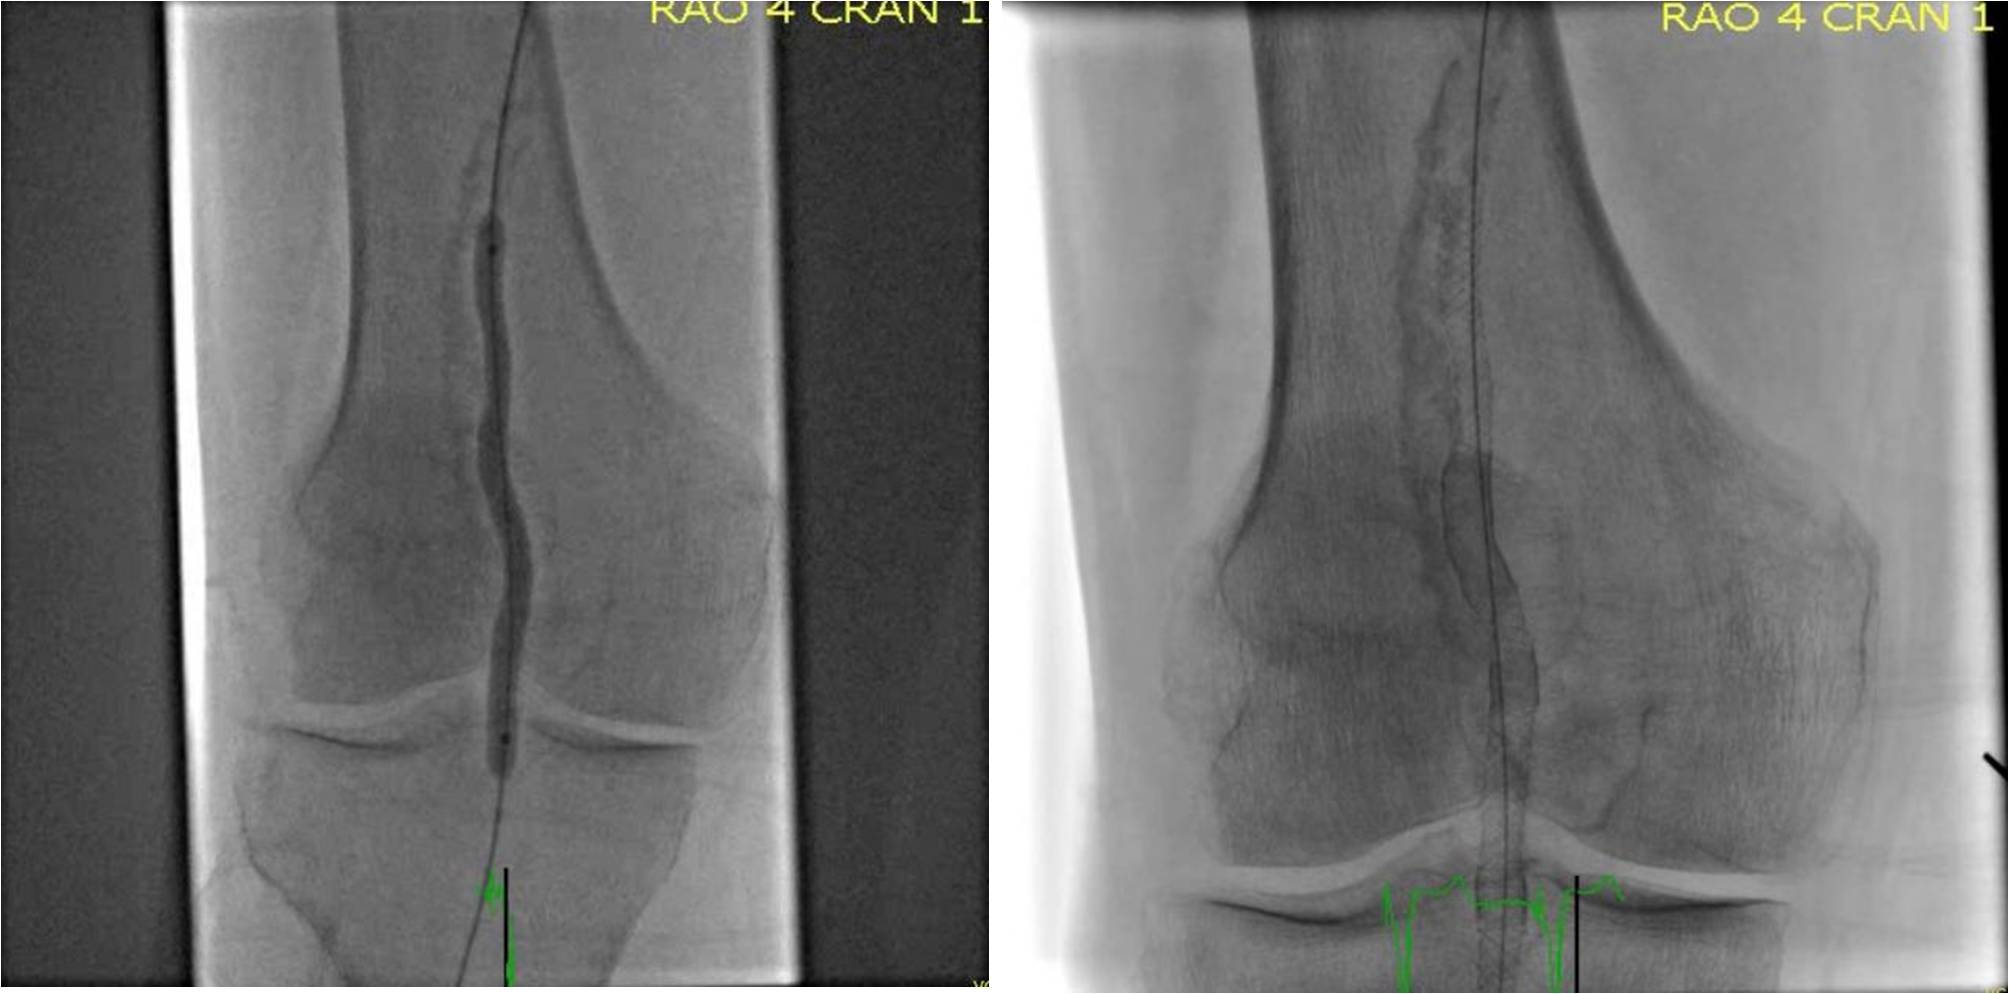

Popliteal kinking is theorized as one of the causes of stent failure in the popliteal space. In an interesting study of 68 patients undergoing angiography of the popliteal artery, a hinge point was identified in 98.6{8ceaa46882e4d49283ff23b35262537230ad541262f55a031ead545e66522058} of patients (Diaz et al. (1), See figure 1).

Because of the intrinsic movement of the knee joint and generation of a hinge point, use of PTA alone, self expanding stents with crush-resistant properties and endovascular stent grafts have been widely studied. The average patency rate of the popliteal artery after PTA alone is approximately 47{8ceaa46882e4d49283ff23b35262537230ad541262f55a031ead545e66522058} at 2 years. The longer the lesion length, the higher the restenosis rates. (reference 1, reference 2, reference 3).

Various trials of self expanding stents in the femoral and popliteal arteries demonstrate an approximate 50{8ceaa46882e4d49283ff23b35262537230ad541262f55a031ead545e66522058} reduction in restenosis at 12 months compared to PTA alone; particularly in those lesions that are TASC A and B (FAST, RESILIENT). Unfortunately, due to vessel flexion and increase torsion at the hinge point, stent fractures are not uncommon and are a current limitation of femoral-popliteal stenting; particularly with current slotted tube nitinol stents which lack sufficient radial strength.